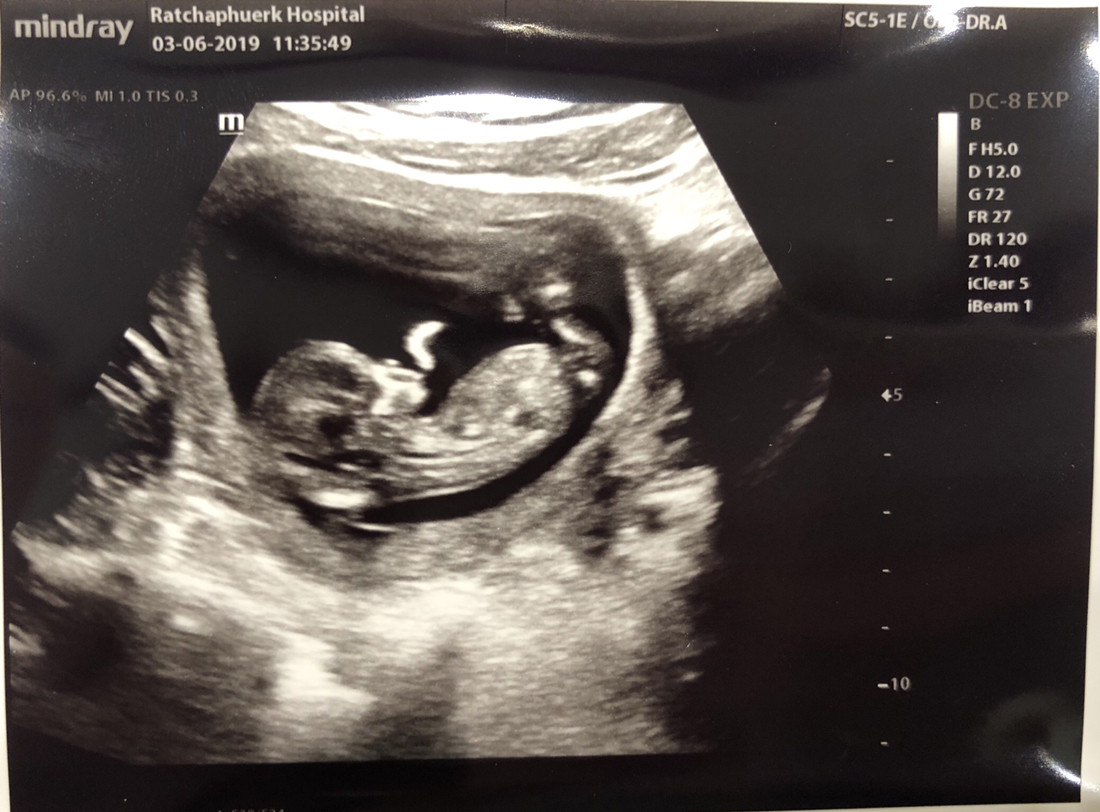

13 วีคค่ะ